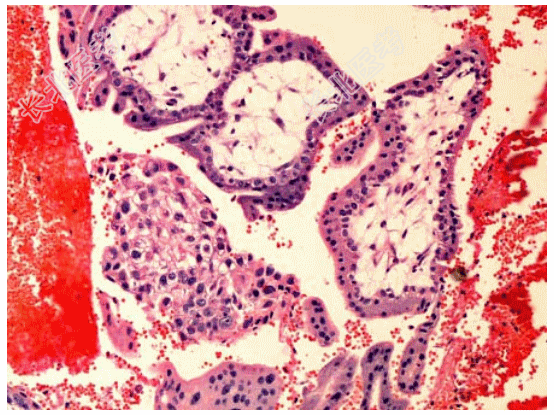

- [材料题] 患者女性,36岁,停经50余天,腹痛一天,后穹窿穿刺少量新鲜血,术中见右输卵管壶腹部膨大并有活动性出血。切除右输卵管,显微镜下所见如图。临床诊断为输卵管妊娠。

- 简答题3、该疾病镜下改变表现为?